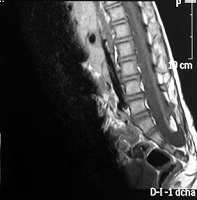

La espina bífida oculta está formada por las malformaciones como los lipomas, senos dérmicos, diastematomielia, etc. que anclan la médula. Se operan con técnicas microquirúrgicas antes del año de vida.